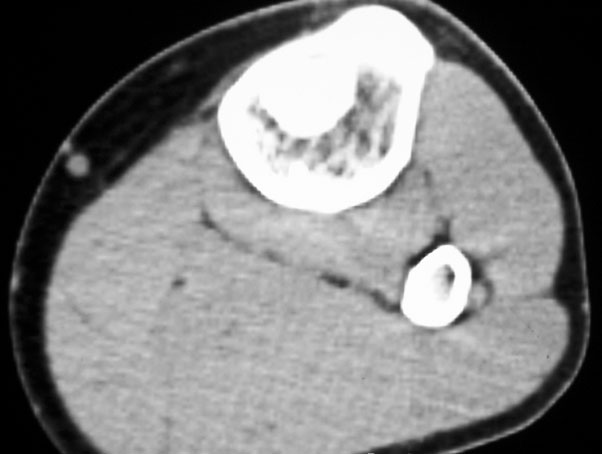

标题: CT19885:左胫骨上端肿瘤。 [打印本页]

标题: CT19885:左胫骨上端肿瘤。

男,20岁,医学院学生,11年前感左胫骨上端劳累后酸痛,曾由父母带到国内好几家有名望的医院诊治,但众说不一,所以基本上没有治疗。今年三月又开始出现症状,又到多家省级医院求治,但专家们的意见还是不能统一。各生化检查正常。mri考虑到胫骨上端良性血管瘤可能性大。ct考虑纤维瘤可能性大。请各位发表高见。